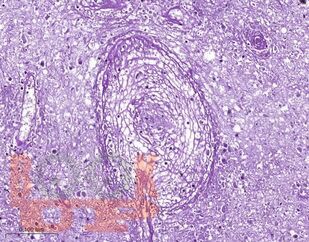

Учебное пособие посвящено актуальным вопросам патогенеза, клинического течения, диагностики и лечения церебрального токсоплазмоза у ВИЧ-инфицированных пациентов. Особое внимание уделено вопросам дифференциальной диагностики церебрального токсоплазмоза от другой патологии нервной системы, в том числе опухолей головного мозга, нарушений мозгового кровообращения, воспалительных заболеваний. В пособии представлены собственные клинические наблюдения многоочаговых и солитарных форм церебрального токсоплазмоза.